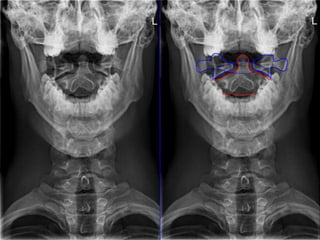

C1 fracture

Jefferson # , is classified into

Stable unstable

Intact Transverse Lig. Ruptured

Transverse Lig.

Dickman greene & sonttag (1996)

classified the TL injury into

Type 1

Disruption of substance of

the ligament

Type 2

Avulsion from the lateral

mass